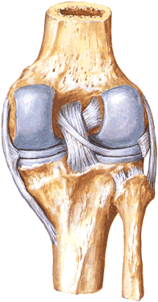

В районе коленного сустава выделяют три главных типа вывихов или подвывихов: голени, менисков, а также надколенника. Полные вывихи голени, как вперед, так и назад или в сторону, являются довольно редким случаем. Колено, сгибаясь только в сагитальном направлении, удерживается от смещения вперед и назад прочными внутренними крестообразными связками: передней (lig. cruciatum anterius) и задней (lig. cruc. posterius).

Боковой вид на надколенник и мениск колена.